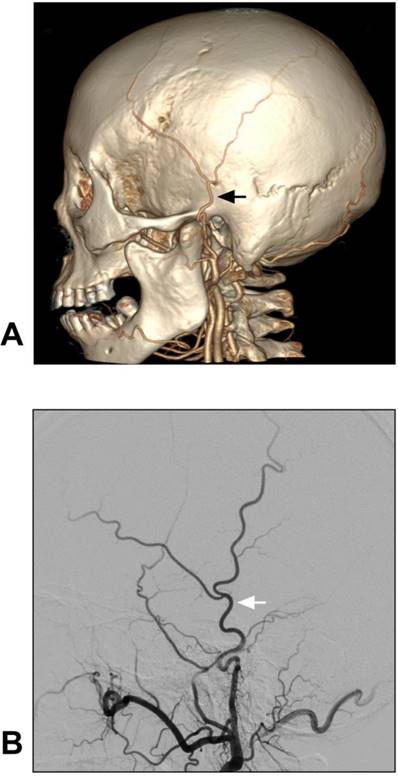

The anatomy of the STA can be evaluated via computed tomographic angiography (CTA) and DSA [20]. The anatomical angiography of the STA is shown in Figure 2.

Figure 2

Anatomy of STA on CTA and DSA. A-B: CTA (A) and DSA images of the ECA (B) show the STA courses over the root of the zygoma before it roughly divides into the frontal and parietal branches. The STA is indicated by black and white arrows in A and B respectively. These CTA and DSA images were obtained from different patients. Abbreviations: CTA: computed tomography angiography; DSA: digital subtraction angiography; ECA: external carotid artery; STA: superficial temporal artery.